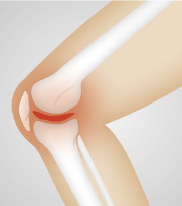

무릎 인공관절이란, 무릎 관절의 손상이나 결손으로 인해 기능이 손상된 환자들에게 수술적인 개입을 통해 삽입되는 인공적으로 만들어진 관절입니다. 인공 관절은 대개 금속, 플라스틱, 세라믹 등으로 만들어지며, 퇴행성 관절질환, 골관절염, 골절, 연골손상 등의 경우에 수술적인 개입을 통해 적용됩니다. 무릎 인공관절 수술은 보통 전체마취를 사용하며, 인공 관절을 무릎 관절에 적용하는 방법은 다양합니다. 수술 후에는 치료 과정이 필요하며, 치료 후에는 신체 활동의 제한이나 운동 요법 등이 필요합니다. 그러나 수술적인 위험성과 치료 후에도 부작용이 발생할 수 있으므로, 수술 전에 신중하게 검토하고 진행하는 것이 중요합니다.

3. 손상된 연골과 뼈를 제거하고 인공관절을 적합한 위치에 고정합니다.